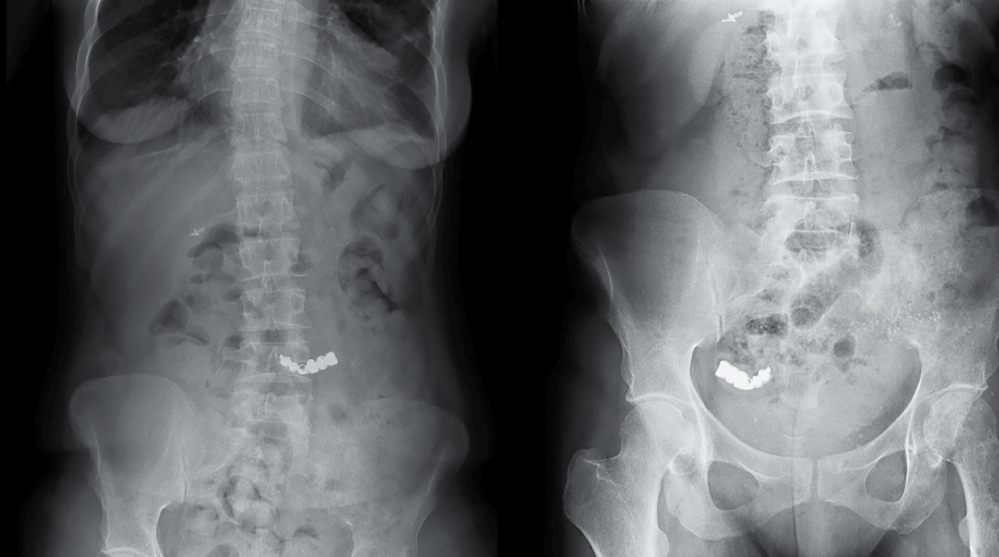

A 44-year-old female presented at the accident and emergency service for having swallowed a dental bridge few hours before during dinner. At the time of the visit, she was completely asymptomatic and no abdominal discomfort was reported. She had no background of mental disorder or misuse of alcohol or other drugs. The ingestion was reported to have happened accidentally and unconsciously. Abdominal x-ray showed the foreign body at the level of the fourth lumbar vertebra, likely to be located in the greater gastric curvature (Figure 1, left panel). The patient was discharged home with recommendation to come back to hospital in case abdominal pain or further concern would have risen.

Figure 1: Abdominal X-ray showing the dental bridge lying in the stomach a couple of hours after ingestion (left panel), and moved onto the terminal ileum a week later (right panel). View Figure 1

Eight days later, she returned at the emergency department still asymptomatic but very worried for not having passed the denture. A new plain film showed the foreign body being moved onto the right pelvis, likely at the level of the last ileal loop (Figure 1, right panel). In the absence of symptoms or signs that may justify an urgent operation, the lady was suggested again to leave the hospital waiting for the dental bridge to pass spontaneously. Currently, no more admission records exist for this patient.